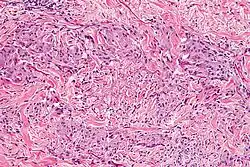

Micrograph showing a palisaded granuloma in a case of granuloma annulare. H&E stain.

Granuloma annulare microscopically consists of dermal epithelioid histiocytes around a central zone of mucin—a so-called palisaded granuloma.[4]